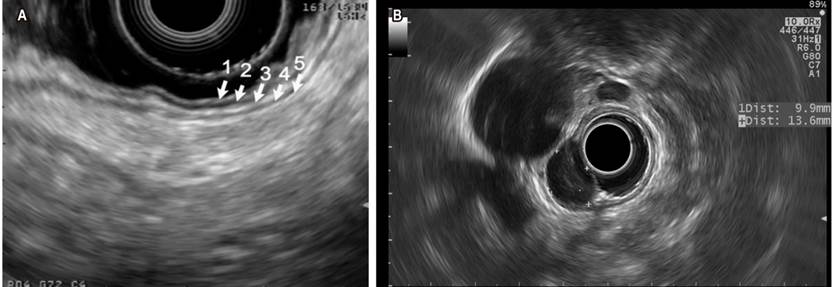

The five main echoic layers can be identified in gastrointestinal wall lesions: the first and second (mucosa, including the muscular layer of the mucosa), the third (submucosa), the fourth (the muscular layer in muscularis propia) and the fifth (serosa or adventitia) (Figure 2A). Endosonography also allows measuring the extent of the lesion and assessing any underlying lymphadenopathy for staging purposes. Gastrointestinal stromal tumor (GIST) is found in the group of lesions that have the potential to become cancerous. Most of them are gastric (accounting for 60% to 70% of all cases) (Figure 2B), with 20%-30% located in the small intestine and slightly less than 5% in the esophagus. In addition to immunohistochemistry (IHC), the aim of tissue collection in the diagnosis of GIST is to obtain material showing spindle cells. The use of CD117, DOG1, S100, CD34, and PDGFRA stains in IHC is recommended since they allow properly differentiating GIST from other subepithelial lesions8. EUS-guided fine needle aspiration/puncture (EUS-FNA) has been traditionally used for collecting the tissue. Its diagnostic performance is highly variable (between 46% and 93%) and is usually limited because the size of the specimen may be insufficient to perform IHC. A recent multicenter study compared the performance of EUS-guided fine needle biopsy (EUS-FNB) to EUS-FNA regarding cytopathology samples collection, the ability to obtain IHC-based diagnosis, and definitive diagnostic performance. Results in cytopathology samples collection were 92 % vs. 46 % (p = 0.001), 89 % vs. 41 % (p = 0.001) in IHC-based diagnosis, and 89 % vs. 37 % (p = 0.001) in definitive diagnosis between the FNB and the FNA groups, respectively, concluding that EUS-FNB outperforms EUS-FNA in terms of histological diagnostic performance of GIST9.

Figure 2 A. Endosonographic view with linear transducer of the echoic layers of the normal gastric wall. B. Homogenous hypoechoic oval lesion corresponding to a GIST of the fourth echoing layer, assessed using a radial transducer. Images taken by Dr. Cañadas, Clínica Marly.